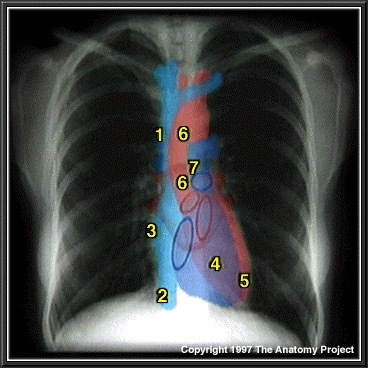

9

Q

What structure is indicated by 1 on the figure below?

A

Superior Vena Cava

10

What structure is indicated by 2 on the figure below?

Inferior Vena Cava

11

What structure is indicated by 3 on the figure below?

Right atrium

12

What structure is indicated by 4 on the figure below?

Right ventricle

13

What structure is indicated by 5 on the figure below?

Left ventricle

14

What structure is indicated by 6 on the figure below?

Ascending Aorta and Aortic Arch

15

What structure is indicated by 7 on the figure below?

Pulmonary vasculature